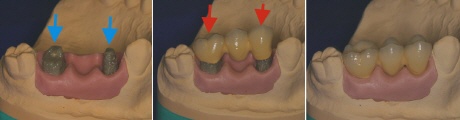

Prinzip Brücke

Für einen fehlenden Zahn müssen zwei gesunde Zähne beschliffen werden. Zum Größenvergleich: Der rechte beschliffene Zahn war vor dem Beschleifen mal genauso groß wie der Zahn rechts neben ihm! Mit Hilfe von Implantaten läßt es sich fast immer vermeiden, dass gesunde Zähne beschädigt werden. Sie sind daher medizinisch in der Regel das Mittel der Wah.l